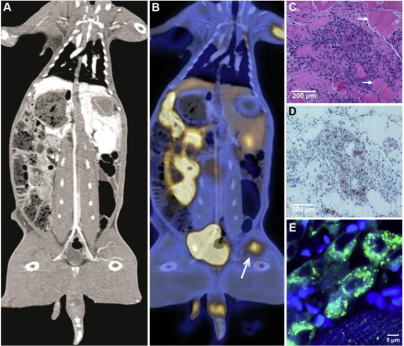

图5  胆固醇结晶栓子引起肌炎。(A)兔左股动脉CC栓塞后的计算机断层扫描图像,保持畅通。(B)48小时PET扫描显示局部炎症(箭头)。(C,D)炎症PET部位的肌肉活检显示巨噬细胞浸润(RAM 11 染色呈棕色)。箭头指向肌肉细胞的收缩坏死。E、荧光显微镜显示巨噬细胞摄取结晶。新鲜样品用Bodipy C-12染色,这是一种对胆固醇具有亲和力的绿色荧光染料,用于突出巨噬细胞内的结晶物质。PET为正电子发射断层扫描。